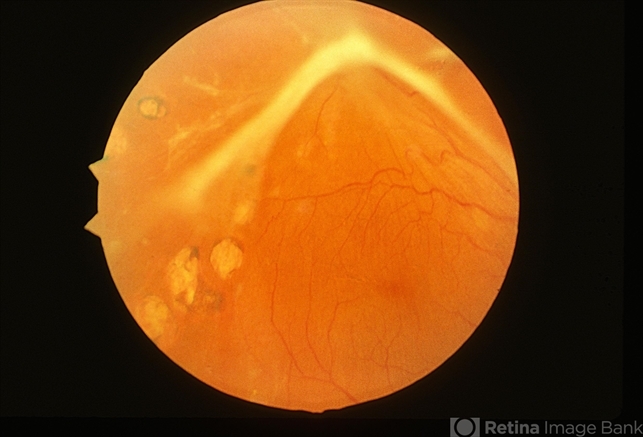

- diabetic traction detachment

- No history, traction retinal detachment, part of stereo pair.